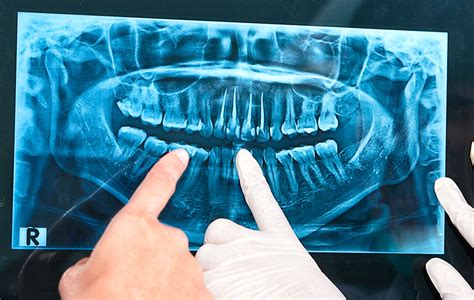

- Ortopantomografía (Panorámicas 2D): También llamada radiografía dental panorámica, es el tipo de radiografía dental más común. Para obtener una panorámica 2D, el paciente se pone de pie o se sienta recto mientras el equipo gira alrededor de su cabeza. Una de las ventajas de las panorámicas 2D es su rapidez. Muestra la totalidad de la estructura facial y mandibular (arcadas superior e inferior, huesos maxilares, mandíbula y estructuras de soporte).